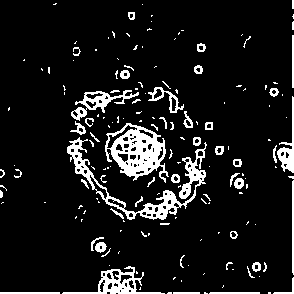

As it was noticed Fig.2(d) is example of low accuracy segmentation. The highly contrast cell core on this image attracts attention, while cell body and boundaries remains shattered. This contrast difference caused by cell morphology since cell itself has no more lens shape and changes to sombrero-hat shape affecting on contrast distribution. Fig.6 demonstrate changes of cell image during processing. As it seen there is high contrast core(actual cell nuclei zone) and almost invisible by eye body of cell with contrast same as in background when it seen by eye. After filtration with G-neighbor and Kuwahara it is appear to became more contrast. However because of values for binarization applied globally for rest of images in sequence it produce false negative recognition 7.

Figure 6: Contrast enhancement as result of filter applying on images of Frame 15.